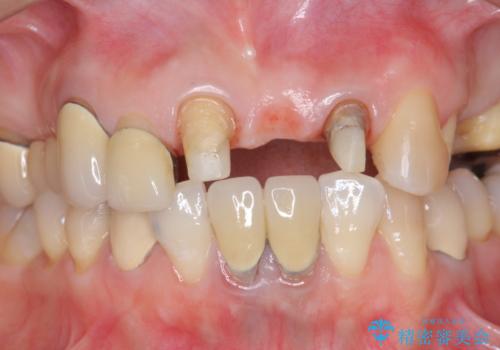

前歯ブリッジのやりかえ

- 前歯の審美障害、見た目の改善を希望され来院されました。

歯肉縁下カリエスも認められるため、挺出を行いセラミックブリッジを審美的に新製します。

- 47万円(仮歯×3・ファイバーコア×2・ジルコニアクラウン×3 歯の挺出)費用は治療当時の料金となります